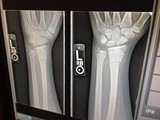

Bone and joint X-rays

If your child has a suspected broken bone or a dislocation, an X-ray may be needed to diagnose the severity of the break.